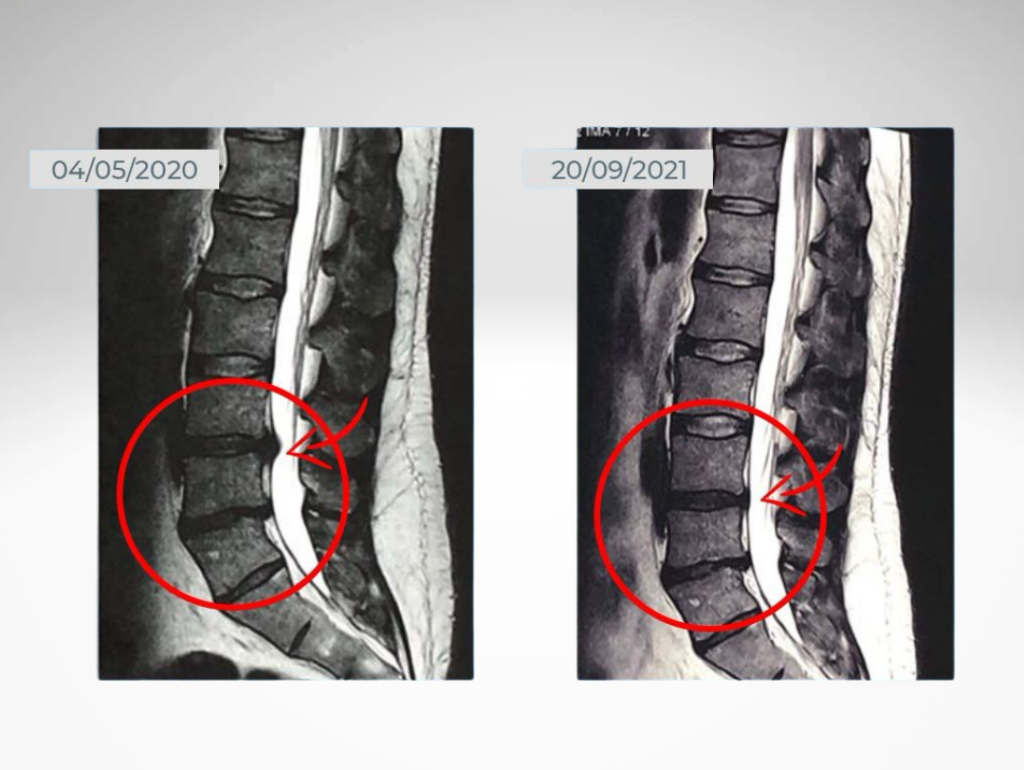

Comparativo de coluna de aluno

Reabilitação Inteligente

A musculação adaptada ao seu quadro clínico acelera a recuperação, melhora a mobilidade e fortalece as áreas afetadas, sempre com acompanhamento especializado.